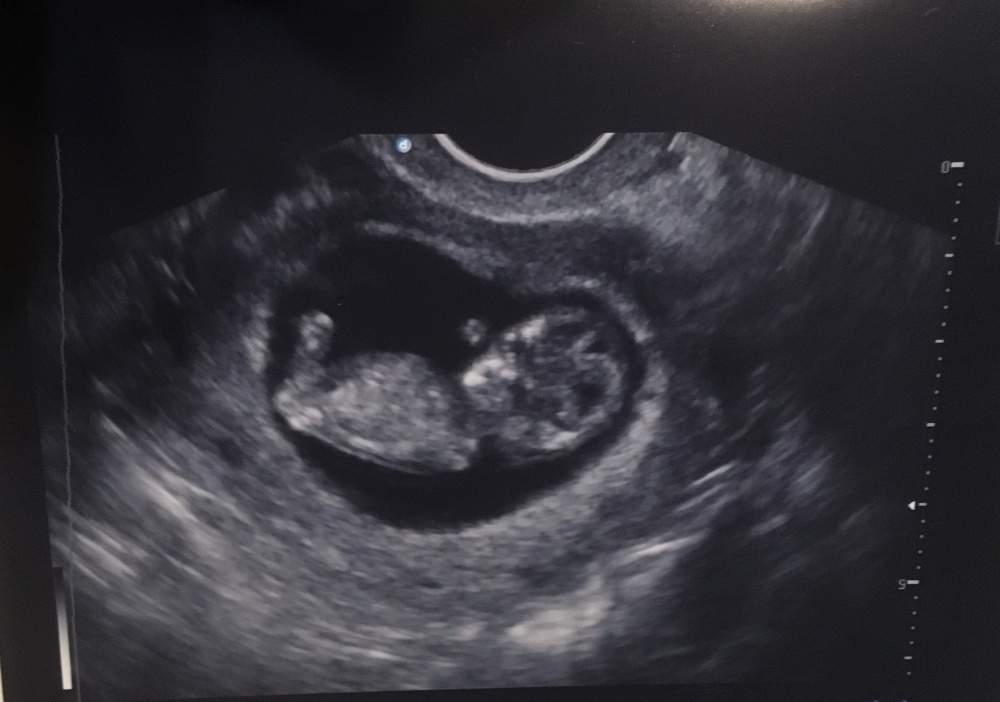

Was meint ihr laut Nub Theorie.

Bild ist von 10+5❤️